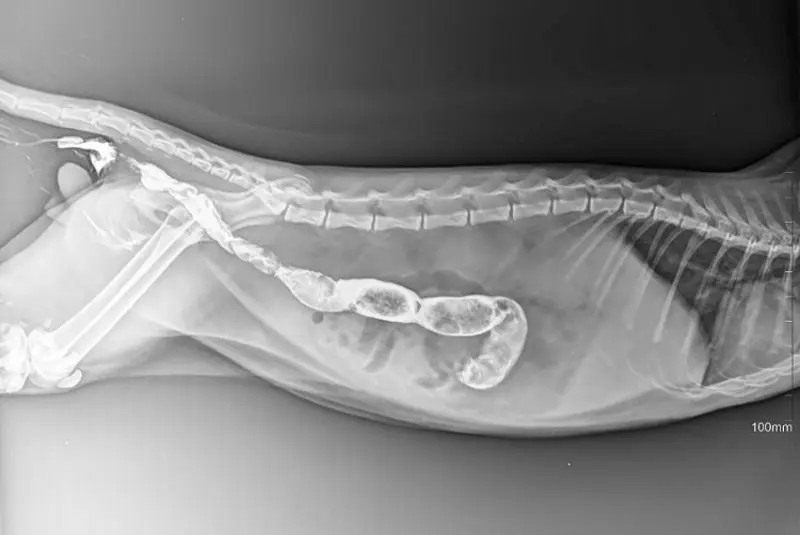

Kliniğimizden Görseller